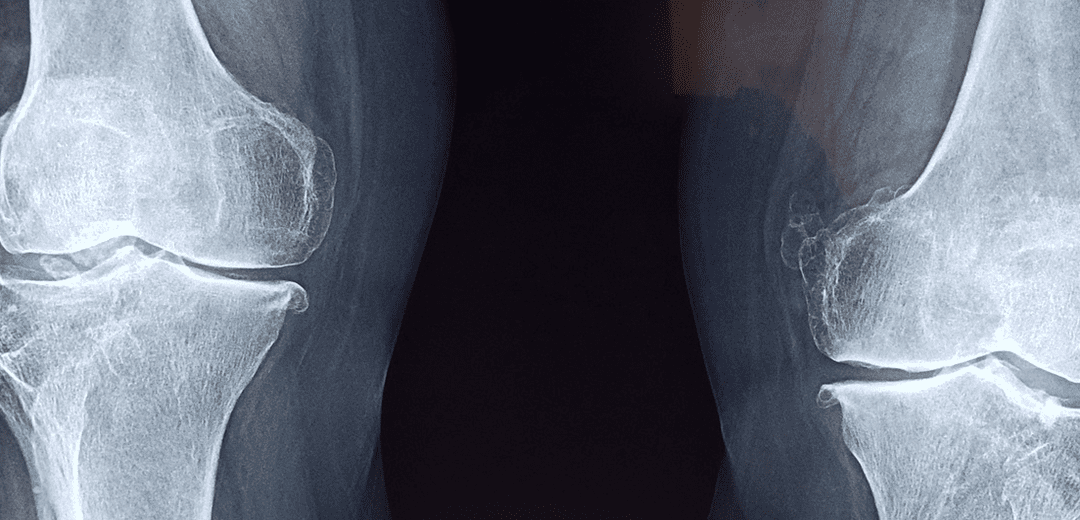

3. 퇴행성 변화

퇴행성 변화는 노화는 함께 발생하는 자연적인 과정으로, 관절 내부의 연골 파손과 변형이 주된 원인입니다. 나이 증가함에 따라 연골은 노화하고 손상되며, 이로 인해 관절 표면 간 마찰이 증가하여 통증을 유발합니다. 또한, 연골 파괴로 인해 관절 내부의 염증 반응이 발생할 수 있으며, 이는 통증과 뻐근함을 느낄 수 있습니다.